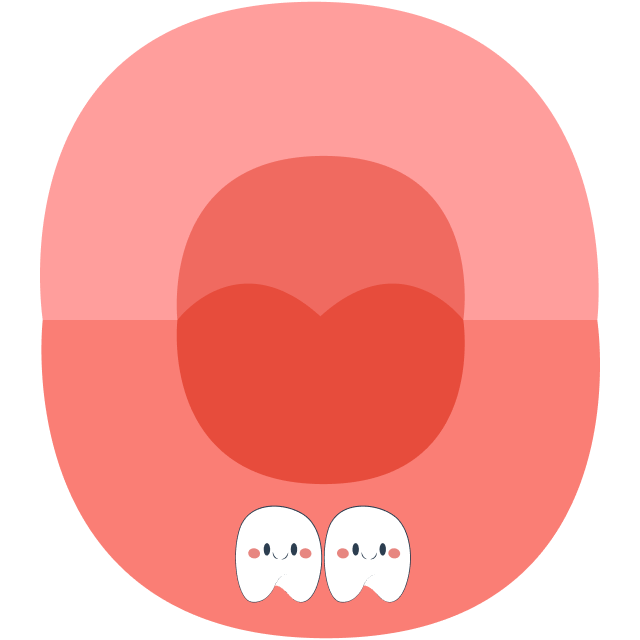

At around 6 years old, children prepare to lose their first tooth, and primary (baby) teeth will gradually be replaced by permanent teeth. The tooth replacement sequence typically begins with the eruption of the first molar (tooth number 6) and ends with the eruption of tooth number 7 around the age of 12.